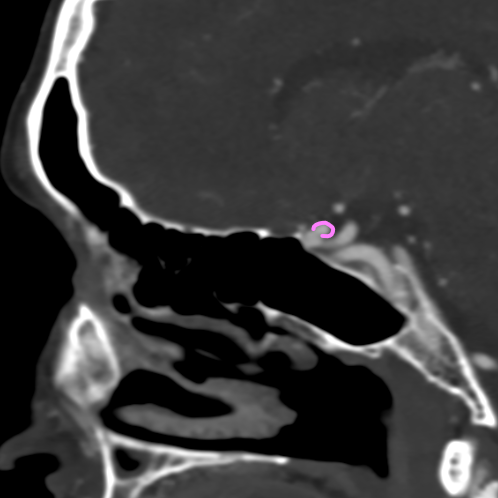

Бусы, о которых поговорим мы, найдены в шее одной из прекрасных пациенток, посетивших меня на КТ.